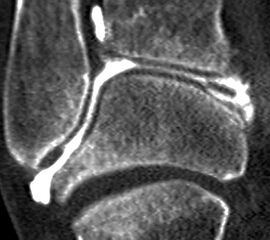

Computertomographie (CT)

Die Computertomographie hat im Laufe der letzten Jahre eine Renaissance in der Diagnostik von chondralen und osteochondralen Läsionen am Talus erlebt. Die Verwendung von Spiral-CT´s (Abb. 7 und 8) mit der Möglichkeit multiplanarer Rekonstruktionen hat die diagnostische Qualität deutlich erhöht 18. Die Stärken zeigen sich insbesondere in der Beurteilung des subchondralen Knochens. In der Diagnostik kleiner Risse mit zystischen Veränderungen in welche Synovialflüssigkeit eindringen kann und daher klinisch bedeutsam ist, zeigt sich eine Überlegenheit gegenüber der MRT-Diagnostik 17. Die im CT abschätzbare Ausdehnung der subchondralen Zyste entspricht im Gegensatz zur MRT mit Abbildung des perifokalen Knochenmarksödems besser dem intraoperativ zu erwartenden Befund 16. Zudem ist die Untersuchungszeit kürzer im Vergleich zum MRT. Allerdings ist eine Beurteilung des Knorpels ohne die Applikation von Kontrastmittel nicht möglich. In einer Vergleichsstudie zwischen MRT und CT in der Diagnostik osteochondraler Läsionen am Talus wurde deshalb nur 81% der osteochondralen Läsionen mit der CT-Untersuchung korrekt diagnostiziert, während dies bei 96% der MRT-Untersuchungen der Fall war. Dafür wies die CT allerdings eine leicht höhere Spezifität auf (99% vs. 96%) 18. Im Vergleich zur MRT-Arthrographie besteht sogar eine höhere Interobserver Reliabilität und leicht bessere Sensitivität in der Entdeckung von Knorpelläsionen 25.